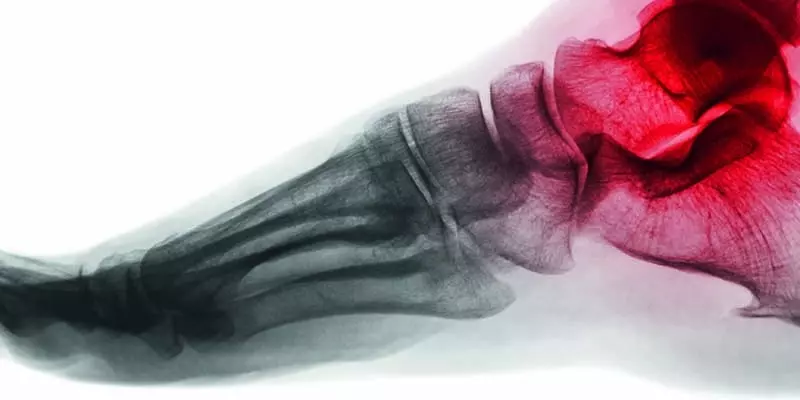

W  obecnych czasach najpopularniejszymi sportami zimowymi są narciarstwo zjazdowe oraz snowboard uprawiane przez dzieci, młodzież oraz dorosłych. Obie te dyscypliny są uprawiane wyłącznie sezonowo w okresie zimowym i przez to większość osób, zakładając narty lub deskę snowboardową na nogi, nie jest odpowiednio przygotowana do sezonu. Sezon zimowy powinien być poprzedzony odpowiednim przygotowaniem motorycznym, tak aby zminimalizować ryzyko wystąpienia kontuzji. Wiele osób w ciągu całego roku nie ma styczności z innym sportem lub jest to rzadki kontakt, co ma znaczny wpływ na poziom przygotowania do sezonu zimowego. Statystycznie urazów snowboardowych jest dwukrotnie więcej niż urazów narciarskich. Jedną z przyczyn jest większa częstotliwość upadków snowboardzistów w porównaniu z narciarzami. Drugą przyczyną takiej dysproporcji jest rodzaj urazów w obu dyscyplinach i moment udzielenia pomocy medycznej. Urazy u snowboardzistów to najczęściej urazy kończyn górnych (nadgarstków), gdzie pomoc udzielana jest na stoku. U narciarzy najczęstsze są urazy skrętne, które często nie są rozpoznawane w momencie urazu i diagnoza stawiana jest wiele tygodni lub miesięcy po urazie jako dolegliwości o nieznanej przyczynie. W przypadku snowboardzistów statystyki mówią o 3−6 zdarzeń na każde tysiąc dni uprawiania dyscypliny. Przeciętny snowboardzista doznaje jednego urazu na każde 190 dni jazdy. Biorąc pod uwagę sezonowość dyscypliny, jeżeli jedna osoba jeździ dwa tygodnie w roku, to według statystyk 1 na 16 lat dozna urazu. Statystyka więc nie wygląda źle, ale jeżeli weźmie się pod uwagę 95 tys. złamań w obrębie nadgarstka w sezonie na świecie, to wygląda to znacznie poważniej. Urazy nadgarstków wśród snowboardzistów stanowią 25% wszystkich kontuzji, w dalszej kolejności są urazy głowy, barków, łokci, a na samym końcu kończyn dolnych. Jeżeli porówna się urazy, które przytrafiają się narciarzom, to problem jest odwrotny. U narciarzy najczęściej występującymi urazami są urazy stawów kolanowych. Na drugim miejscu są urazy kończyn górnych, a w dal...